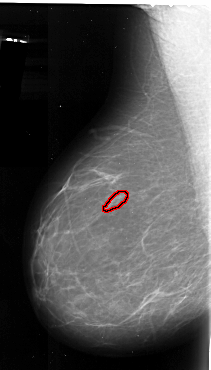

A_1083_1.LEFT_CC

LEFT_CC LINES 5056 PIXELS_PER_LINE 3571 BITS_PER_PIXEL 16 RESOLUTION 42 OVERLAY

FILE: A_1083_1.LEFT_MLO.OVERLAY

TOTAL_ABNORMALITIES 1

ABNORMALITY 1

LESION_TYPE CALCIFICATION TYPE PLEOMORPHIC DISTRIBUTION LINEAR

ASSESSMENT 4

SUBTLETY 2

PATHOLOGY MALIGNANT

TOTAL_OUTLINES 1

BOUNDARY